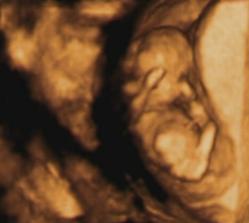

Moj prvy pokladik